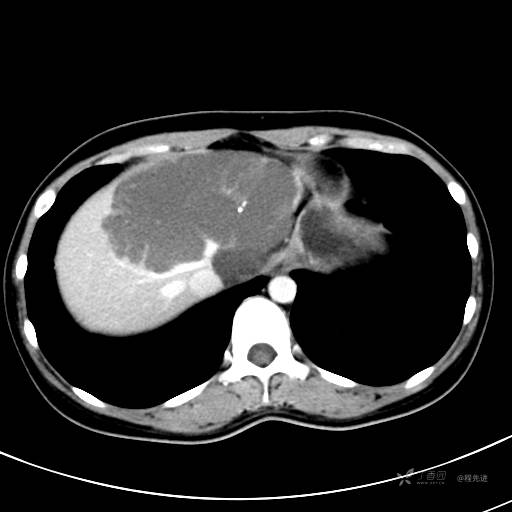

CT平扫+增强,每个序列3张图

CT值 平扫48HU 动脉期66HU 静脉期68HU 延迟期62HU